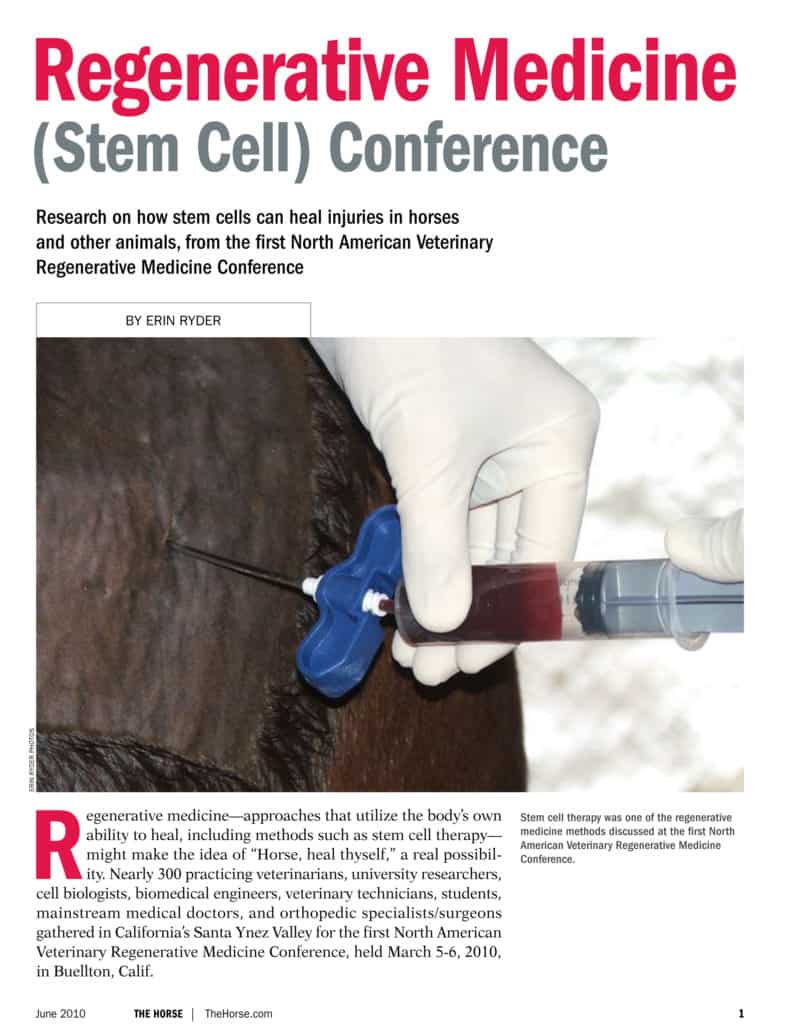

Dr. Duncan Peters of the Hagyard Equine Medical Institute discusses regenerative therapies (such as stem cell therapy and platelet-rich plasma) for healing injuries common to sport horses.

Regenerative medicine (stem cell therapy) might make the idea of “Horse, heal thyself,” a real possibility. This was the topic at the first North American Veterinary Regenerative Medicine Conference in 2010.